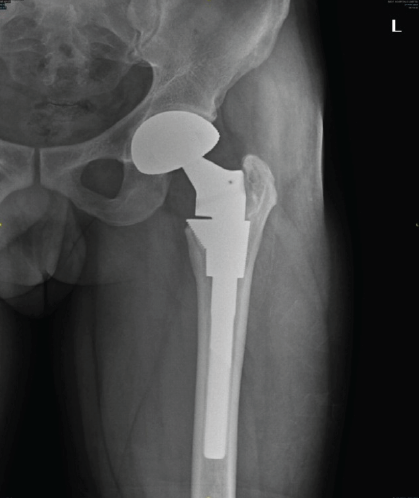

The patient is walking full weight bearing without support and is able to carry out all his daily activities without any discomfort. Patient’s pre-operative Harris hip score (HHS) was 20, which was improved to 86 at the latest follow-up. There was no evidence of recurrence of tumor noted clinically and radiologically [Fig. 6].

Figure 6: 2 year follow-up X-ray showing no evidence of any loosening and ossification in medial border of trochanter.

GCT of the bone is one of the most commonly discussed tumors with a lot of controversies ranging from its etiology to its management. The exact histogenesis of GCT is not well known, and the correlation between its histology and its clinical course is undefined [8,9,10,11]. Even though Campanacci’s classification is used to grade the tumor, many studies have demonstrated no correlation between Campanacci grade of the tumor and the risk of local recurrence or metastasis, hence it cannot be used a single prognostic factor [12]. There are differences of opinion regarding the exact management, with many authors recommending achieving a proper local control and maintaining the function. Hence, EC using high-speed grinding and drilling to remove the invaded bone has been recommended. Adjuvants such as phenyl alcohol, iodine, hydrogen peroxide, or zinc chloride have been used by many authors to reduce the post-operative recurrence rate [13,14]. These adjuvants help to remove the tumor cells which were left behind after the curettage either by their thermal (liquid nitrogen, methyl methacrylate) or by chemical reaction (phenyl alcohol, H2O2). There is also a difference of opinion regarding filling the cavity after EC. Kivioja et al. in their study about the use of cement after intralesional curettage in GCT in 294 patients with a median follow-up of 5 years had shown a 0.2% recurrence rate with cement and 0.56% without cement. They recommended the use of cement as a good prognostic factor [8]. On the contrary, Turcotte et al. in their 186 patients, found no statistical significance between the use of adjuvant and filling material with the risk of local recurrence [10]. Some studies even reported thermal necrosis of the articular cartilage and non-fusion of the cement subchondral interface after use of cement. Hence, allogenic bone transplantation (3 mm–10 mm thickness) was advocated, and it is soaked in H2O2 to remove its immunogenicity [15]. GCT of the proximal femur has low incidence, high recurrence rate after curettage, and more local invasiveness with strong bone destructiveness leading to pathological fracture [16]. EC or SR is the two most commonly used procedures for these tumors. The use of high-speed burr in EC in tumors around the femoral neck is difficult because of thin quality of bone due to tumor destruction and may lead to increased risk of pathological fracture [17]. On the other hand, SR and reconstruction usually result in poor functional outcome and increased risk of complication hence it is difficult to decide whether to do SR and reconstruction to minimize the local recurrence versus to preserve the joint with a more conservative approach [18,19]. Yuan et al. did a comparative analysis between EC and SR in GCT of the proximal femur, showed 5.3% recurrence rate in EC group and 10% in SR group in 29 patients. They recommended EC in patients without extensive soft tissue and articular surface involvement and patients without pathological fracture for better functional outcome and survival. In other cases, SR is recommended. Denosumab inhibits RANKL pathway, which in turn inhibits osteoclast activation and prevents osteolysis. After denosumab treatment mononuclear cells and giant cells disappear, there is partial maturation of neoplastic stromal cells to osteoblastic cells and fibrous cells, which also helps to form osteoid matrix. Denosumab helps to reduce the size of the tumor, forms calcified ream around the soft-tissue components, thus helping to do a local control, allowing EC with adjuvants or en bloc resection with endoprosthetic replacement possible in previously unresectable tumors. It is also indicated in the treatment of axial bone GCT, where surgery is difficult. Hence, the use of denosumab has been recommended as a neoadjuvant agent [12]. Its use has been approved by the Food and Drug Administration in 2013 for patients with GCT who are either inoperable or surgery may cause unacceptable morbidity, or in patients with metastatic disease. In our patient, the extent of involvement of the tumor was primarily in H1 and H2 areas with minimal involvement in H3 area in the left proximal femur with cortical dehiscence in the superolateral aspect of the femoral head and anterior and posterior cortices of the femoral neck. Patient’s mobility was also limited for the past 5 months. EC was not considered as a treatment option due to the extent of involvement, breach in the femoral head-and-neck cortices, and this area being prone to high recurrence rate and pathological fracture. SR was not considered since the patient was young, and this procedure has a high complication rate and poor functional outcome in the long term. Hence, it was decided to use a combined approach, i.e., near total excision of the tumor, EC of the remaining portion of the involved area of greater and lesser trochanter, and THR using hip prosthesis, followed by systemic therapy using injection denosumab 120 mg subcutaneously postoperatively once a month for 12 months. Denosumab injection helped in the ossification of the curetted area around the trochanteric region. At the end of 3 years of follow-up, there is no evidence of any recurrence of the tumor with improved patient’s functional outcome (patient’s pre-operative HHS was 20, which was improved to 86 at the latest follow-up). Hence, this combined approach of local clearance of the tumor by surgery and systemic adjuvant denosumab injections helped us to achieve a successful outcome. However, a complete prospective case series with long-term follow-up will throw more light on the usefulness of this procedure.